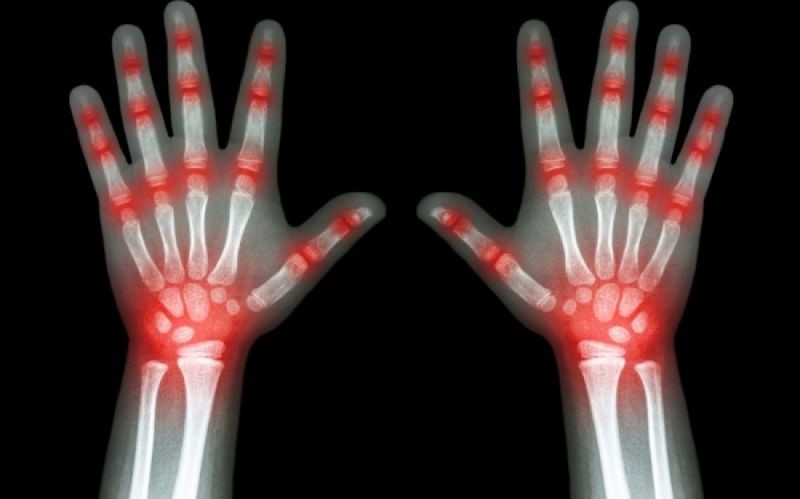

Η αρθρίτιδα έχει δυο τύπους. Την οστεοαρθρίτιδα και την ρευματοειδή αρθρίτιδα. Και τα δυο μπορούν να φέρουν πολύ έντονους πόνους στις αρθρώσεις.

Όταν κάποιος πάσχει από αρθρίτιδα, σημαίνει πως στο σώμα του υπάρχει φλεγμονή. Κι αυτή επηρεάζεται από την διατροφή.